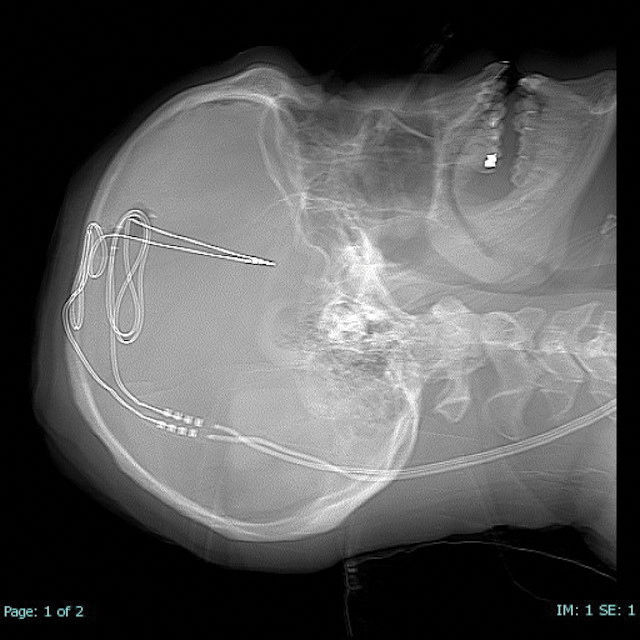

Οι γιατροί τον ενημέρωσαν ότι θα του ανοίξουν δύο τρύπες στο κρανίο, από όπου και θα εισάγουν ένα ηλεκτρόδιο στην κάθε μία, το οποίο θα είναι συνδεδεμένο με έναν βηματοδότη. Ο βηματοδότης θα εμφυτευόταν κάτω από το στέρνο του και θα έστελνε ηλεκτρικά κύματα στον εγκέφαλό του, τα οποία θα σταματούσαν την επιθυμία του για λήψη ναρκωτικών.

Το μεγαλύτερο χρονικό διάστημα της ζωής του που κατάφερε να διακόψει τη λήψη απιοειδών ήταν δύο μήνες. «Οταν όμως οι γιατροί από το Ινστιτούτο Νευροχειρουργικής του Πανεπιστημίου Ροκφέλερ στη Δυτική Βιρτζίνια μου τοποθέτησαν τον βηματοδότη εγκεφάλου και τον έθεσαν σε λειτουργία, τότε ένιωσα αμέσως τα αποτελέσματά του», σχολιάζει ο ίδιος.

Πρόσφατα, μάλιστα, ενημερώθηκε και το λογισμικό της συσκευής που ανοίγει τους διεγέρτες εγκεφάλου για να προκαλέσουν ηλεκτρικό σήμα στον εγκέφαλό του και πλέον οι γιατροί μπορούν και παρακολουθούν και καταγράφουν τα δεδομένα.

«Η τεχνική και τα ηλεκτρόδια που χρησιμοποιούνται για να διεγείρουν εν τω βάθει τον εγκέφαλο είναι τα ίδια στη νόσο του Πάρκινσον και στον εθισμό στα ναρκωτικά, όμως διεγείρουμε διαφορετικά σημεία του εγκεφάλου κατά περίπτωση», εξηγεί ο Ρεζάι.